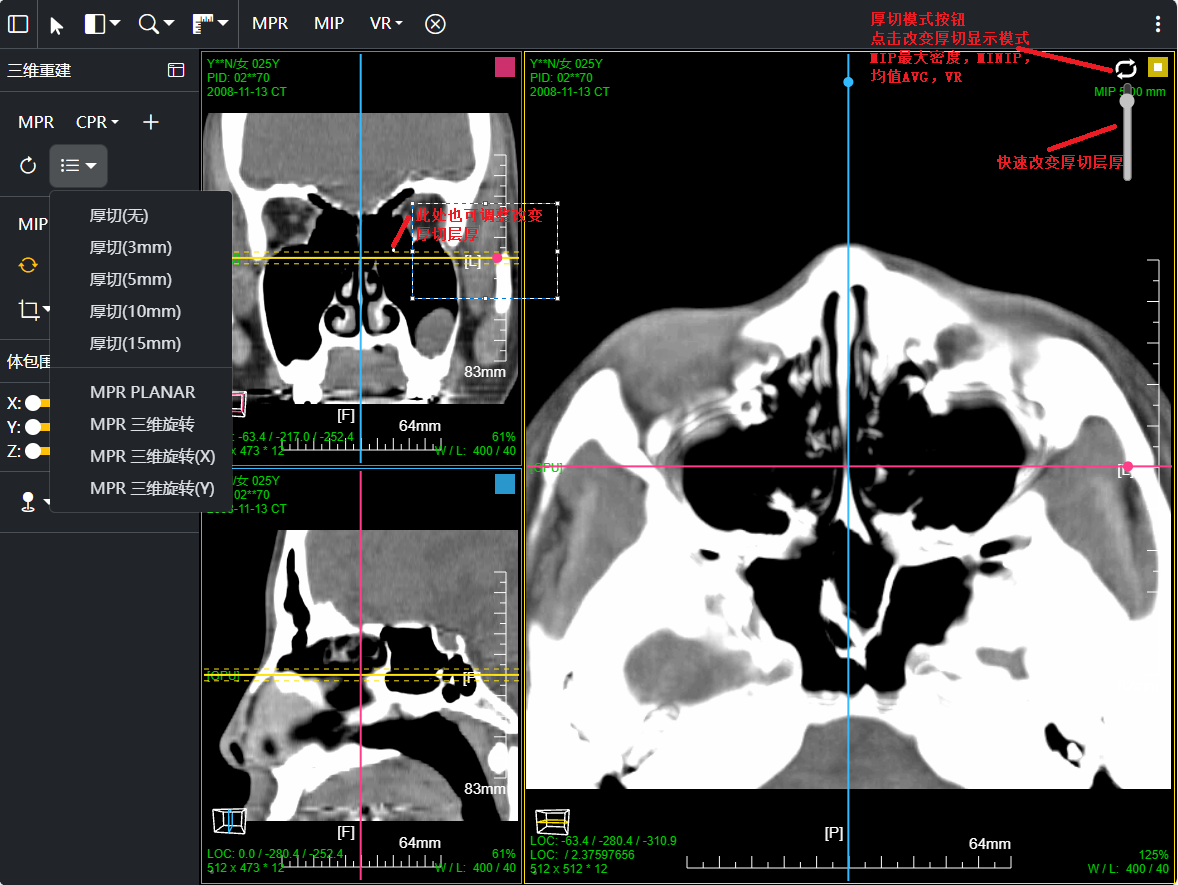

三维:MPR多平面重建(支持任意旋转)、CPR任意曲线切面重建、MIP最大密度、VR容积重建、VE虚拟内窥;任意三维裁剪、一键去床、一键去头骨、快速旋转、厚切MPR(最大密度/最小密度/均值/VR); 手工/半自动分割,分割目标三维渲染; 肋骨CPR拉伸渲染、牙神经管渲染、血管CPR拉直渲染等

八、三维浏览功能操作和截图

左键双击MPR窗口可在MPR三窗口和1x1窗口间切换;三维渲染窗口左键双击在在1x1视图模式和当前视图模式切换

点击MPR窗口右上角颜色块可AXIS轴位、CORO冠位、SAGI矢位切片切换

CPR曲面重建 、厚切曲面;